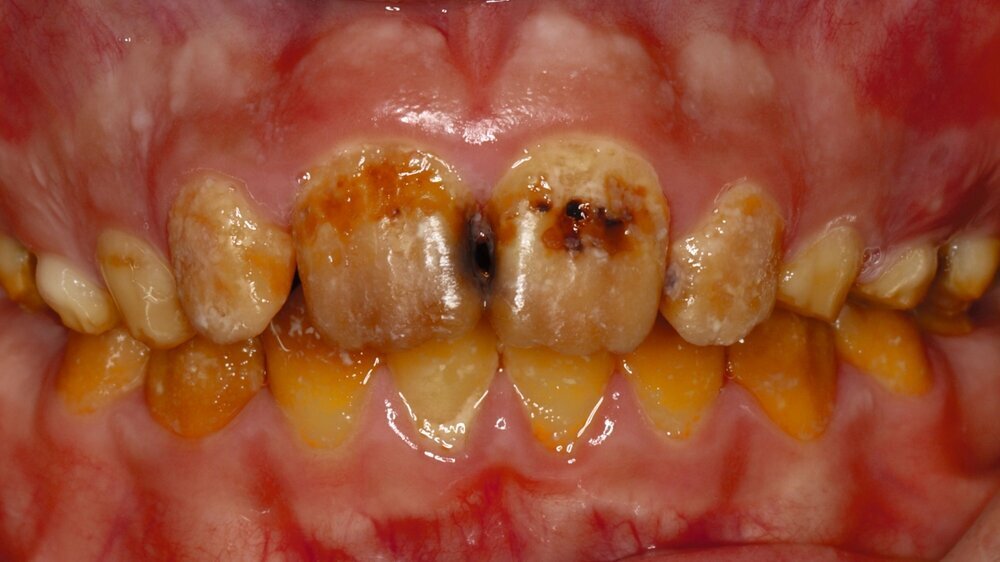

Klinisch zeigte sich ein kariöses Wechselgebiss mit generalisierten Verfärbungen und rauer Schmelzoberfläche. Mehrere Milch- und bleibende Zähne wiesen aktive kariöse Läsionen auf. Zahn 64 war zusätzlich druckdolent und gelockert, mit einer vestibulären Schwellung der Gingiva. Zudem bestanden eine Mittellinienabweichung, ein Overbite von vier Millimetern und ein Overjet von elf Millimetern (Abbildung 1). Extraoral fiel ein fliehendes Kinn mit inkomplettem Lippenschluss und hyperaktivem Musculus mentalis auf. Röntgenologisch waren alle Zähne angelegt, der Zahnschmelz zeigte jedoch eine reduzierte Opazität (Abbildung 2). Eine genetische Abklärung wurde von den Erziehungsberechtigten aus ethischen Gründen abgelehnt.